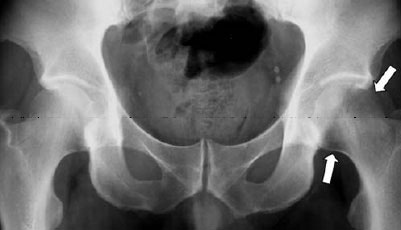

Ακτινογραφίες

Οι απλές ακτινογραφίες μπορούν να δείξουν καθαρά την οστική απώλεια μόνο όταν η νόσος βρίσκεται σε αρκετά προχωρημένο στάδιο (μετά τους 2-3 μήνες). Στις εγγύους καλό είναι να αποφεύγονται.